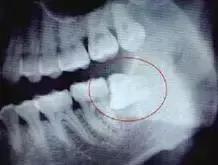

阻生牙拔除术步骤和方法 (下颌阻生智齿拔除的并发症)

高位阻生一般不须切开,或仅在远中切开、分离牙龈即可;中低位阻生最好选用袋形瓣切口,也可选用三角瓣切口。阻生牙若埋藏很深,也可选用三角瓣切口。

去除全部牙合面和部分颊侧、远中的牙槽骨。一般原则:显露牙冠最大周径;尽量保持颊侧皮质骨高度;根据拔除难度及切割牙冠方式确定去骨量。为保持牙槽骨高度,颊侧及远中去骨时可仅磨除贴近患牙的部分。为保护舌神经、第二磨牙及其牙周骨质,原则上不去除舌侧及近中牙槽骨,远中不超中线,将分离器置于远中骨板周围进行保护。

去骨时先确定最小的去骨量,一般垂直阻生去骨或增隙须达牙冠外形高点以下;水平和近中阻生应达近中颊沟之下,以便分切牙冠;远中阻生至远中牙颈部以下,以便消除远中阻力。

包括截冠和分根。其目的是解除邻牙阻力、减小根部骨阻力。常用方法为用钻从患牙牙冠颊侧正中向舌侧进行纵向切割达根分叉以下,将牙分成近、远中两部分(为保护舌侧软组织及舌神经,通常切割至余留患牙舌侧少部分牙体组织即可)。近中部分仍存在邻牙时,可在近中部分釉牙骨质界处做一横断切割,将其分割为牙冠和牙根两部分先后取出。多根牙可将其牙根分割成单根后再分别挺出。